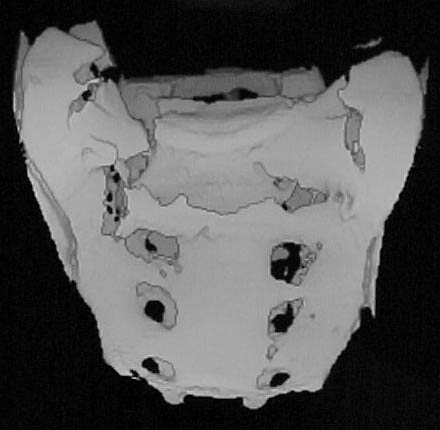

A 28 year old male jumped from the 4th floor on 11-25-2000 sustaining an L1 burst fracture that has been fixed anteriorly by the neurosurgeon with a strut between T12 and L2. A Kaneda device was placed anteriorly as well. My concern is the pelvic ring injury. There are bilateral sacral fractures through the foramen and a transverse element through the sacrum between S2 and S3. the lower part of the sacrum is displaced forward. Anteriorly there are right superior and inferior pubic rami fractures.

3D